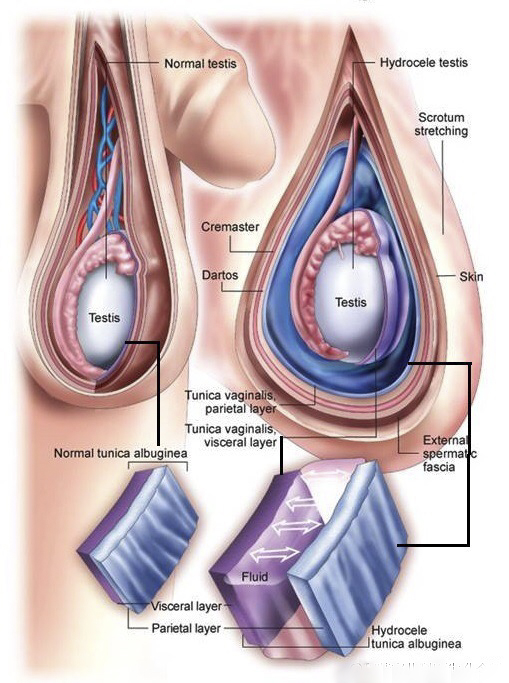

A:睪丸鞘膜積液的危害,包括鞘膜積液進行性的進展加重,可能會導致患者出現疼痛、墜脹,甚至可以影響睪丸的血運和溫度,引起睪丸的萎縮,甚至雙側積液可以影響生育能力。通常睪丸積液可能與創傷、炎症,或者心功能不全、腹水等相關。在臨床上對於睪丸鞘膜積液……

A:正常情況下睪丸鞘膜腔內是可以有一些液體的,保證睪丸在陰囊內具有一定的活動範圍,隨著睪丸陰囊鞘膜腔的液體增加,我們稱之為鞘膜積液。鞘膜積液可以分成睪丸鞘膜積液、精索鞘膜積液或者混合型的鞘膜積液,以及交通性鞘膜積液和嬰幼兒的鞘膜積液,鞘膜積液在……